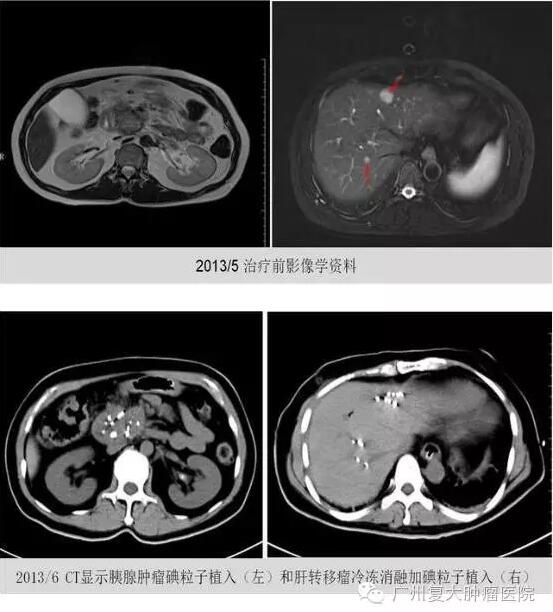

● 2013年5月6日就诊于我院。当时CEA 206 mg/ml,CA19-9值为975 u/ml。给予区域性动脉灌注化疗:吉西他滨1.6 g加顺铂80 mg;胰腺肿瘤经皮冷冻消融加125碘粒子35粒植入。术后第4天复查,CEA降至136 mg/ml,CA19-9 降至474 u/ml;

● 2013年6月26日,给予胰腺肿瘤碘粒子植入、肝转移瘤冷冻消融以及碘粒子植入。口服替吉奥 40 mg,一日两次,一年后自行停服;